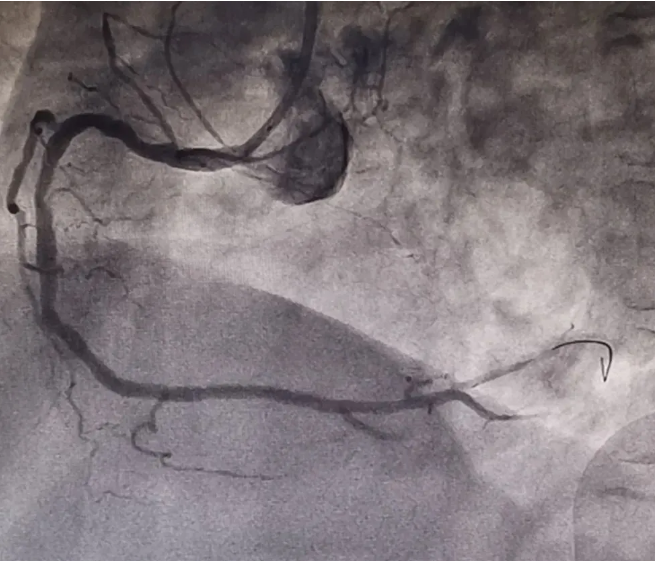

放射科、介入诊疗室、心血管科与急诊科紧急联动,迅速会诊,制定急性心肌梗死介入治疗手术方案,在冠脉造影检查过程中发现,患者右冠状动脉中断完全闭塞,病情十分危急!李友文主任医师迅速将导丝通过闭塞血管,并及时给予替罗非班血管注入,减轻血小板的聚集,抑制血栓形成,促进再灌注形成;球囊通过后给予后适应处理,防止再灌注心律失常的发生。整个手术过程顺利,成功为患者植入一枚支架,用时40分钟,患者术后恢复良好。

迄今为止,冠脉造影仍然是诊断冠心病的“金标准”,可以直观的观察到冠脉血管的狭窄程度,最重要的是,一旦发现严重狭窄的病变,可以随即行支架植入术或球囊扩张术进行治疗,“一站式”完成从确诊到治疗的过程,十分高效。而且,冠脉造影属于微创手术,在局麻下即可进行。